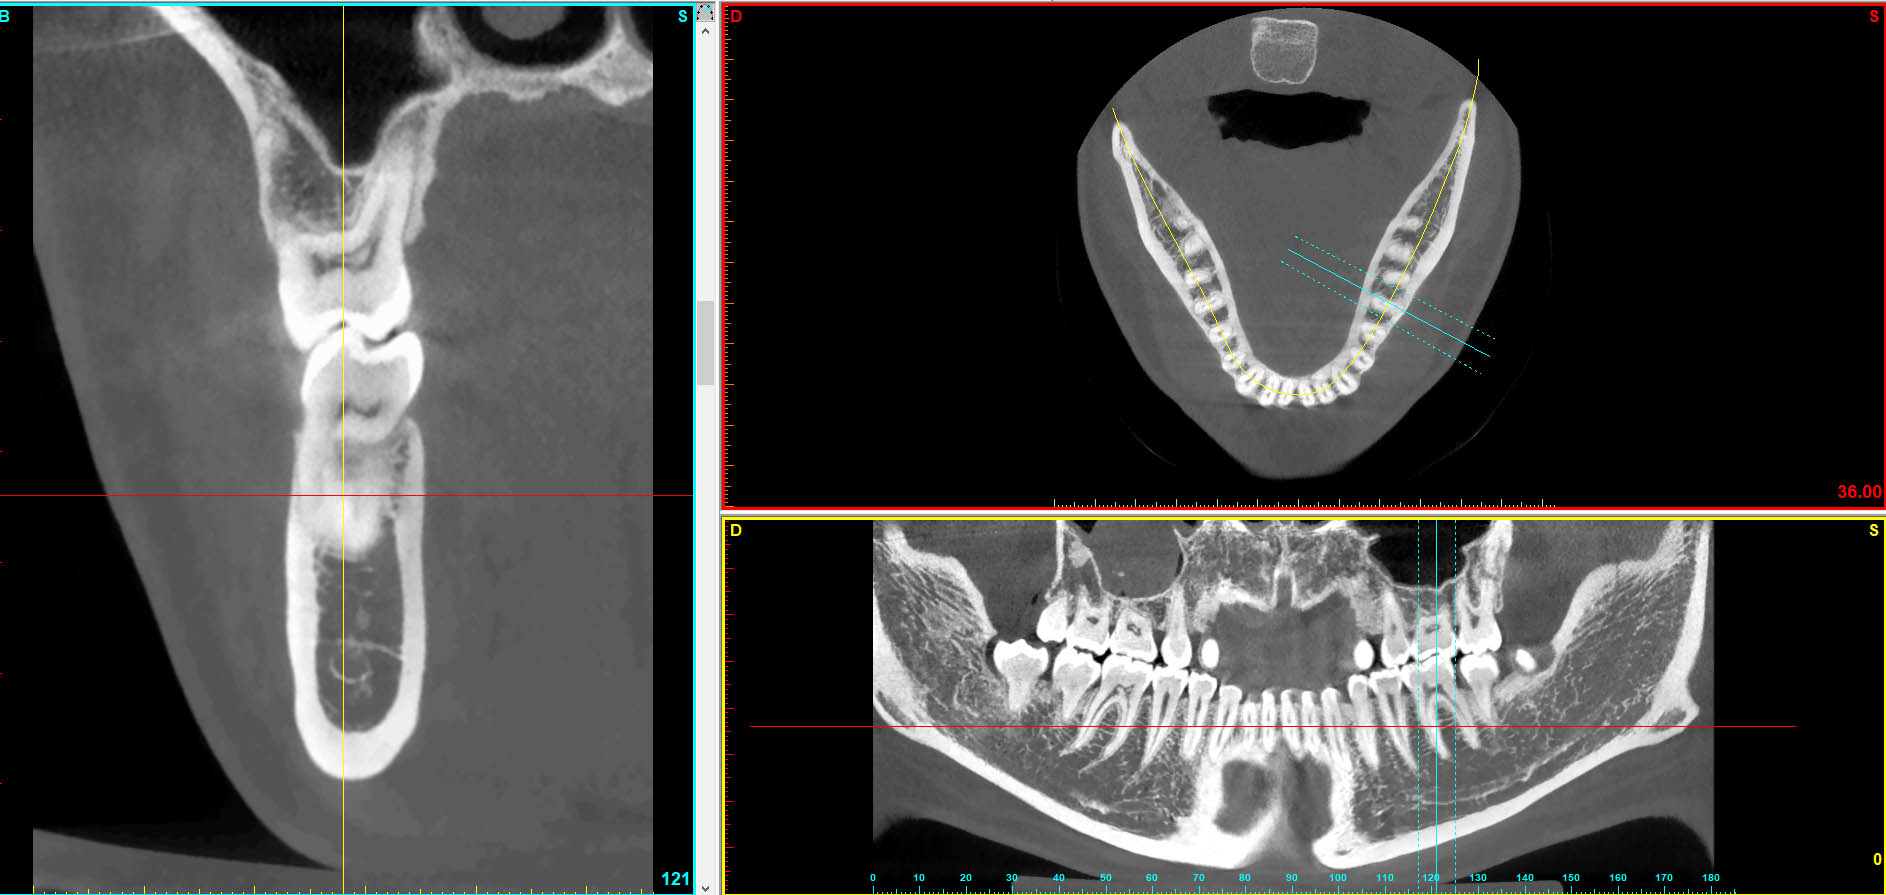

Dentascan

Il paziente e’ posizionato su un lettino che scorre all’interno di un grande anello dove e’ contenuto il tubo radiogeno;questo ruota intorno al paziente emettendo radiazioni ionizzanti che attraversano il corpo del paziente e vengono rilevate da una corona di detettori;questi ultimi inviano i segnali ad un computer che li elabora fornendo immagini bidimensionali del piano di scansione studiato sul monitor.

La durata dell’esame è di pochi minuti.

Attraverso l’utilizzo di una Tac Spirale è possibile effettuare l’esame Dentascan.

Il Dentalscan (Dentascan o TC dentale) è un’applicazione della TAC e si esegue con un software di ricostruzione delle immagini dedicato allo studio delle arcate dentarie.

E’ un valido supporto nella pianificazione terapeutica, nella valutazione e nel follow up delle procedure di implantologia.

Mediante software di ricostruzione dedicati allo studio multiplanare e 3D delle arcate dentarie è lo strumento più efficace per definire con precisione la quantità e la qualità dell’osso su cui effettuare gli impianti.